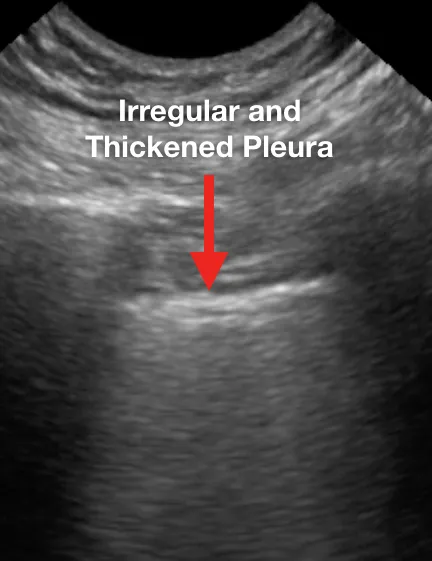

1. Утолщение плевральной линии с неравномерностью плевральной линии;

Ниже представлен ряд изображений патологических изменений, которые Вы можете увидеть при УЗИ легких пациентов с COVID-19. Эти изменения можно найти в любой части легкого, поскольку COVID-19 имеет мультифокальное распределение. Возможно сочетание областей нормального легкого и области с патологией. Патологические изменения легких могут отсутствовать в начале заболевания и при легком течении COVID-19, однако, по мере его прогрессирования, Вы можете наблюдать всё больше патологических изменений.

Ниже приведены примеры УЗ-картины легких пациентов с COVID-19.

Прерывистая и неравномерно утолщенная плевральная линия